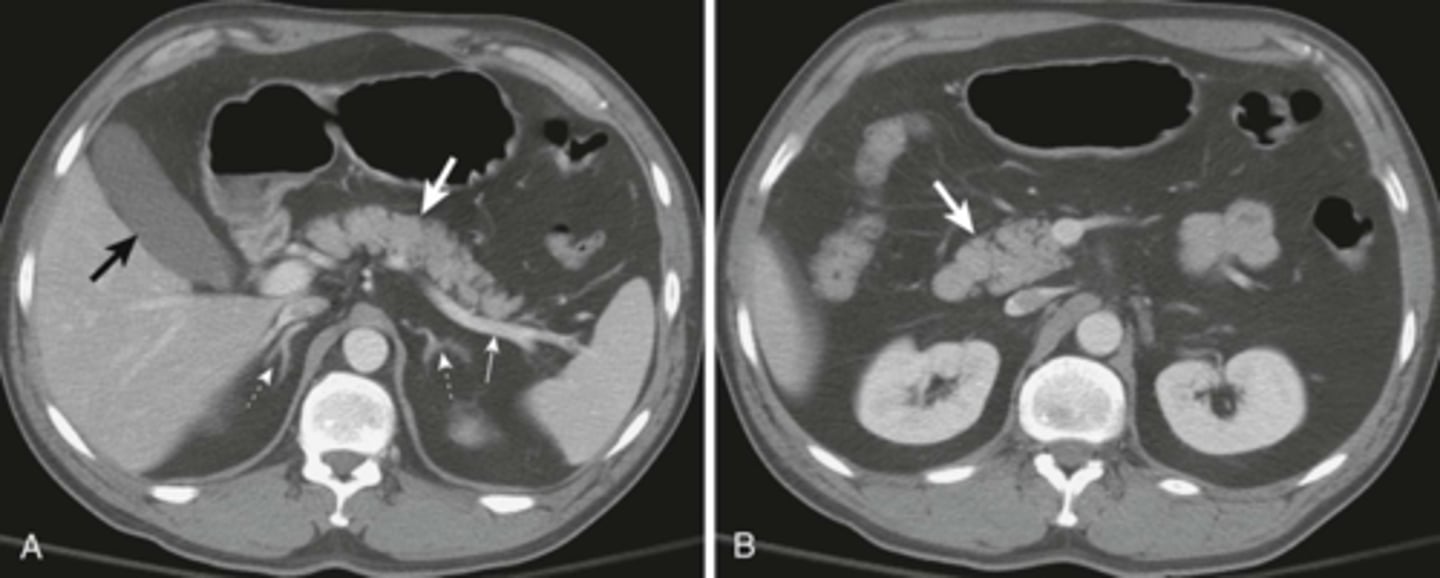

CT small bowel obstruction

, secondary to crohn's dz

CT with IV contrast of SBO.

SOLID BLACK ARROWS: multiple fluid- and contrast filled dilated loops of small bowels.

WHITE ARROWS: Collapsed colon

DOTTED BLACK ARROW: Right renal cyst